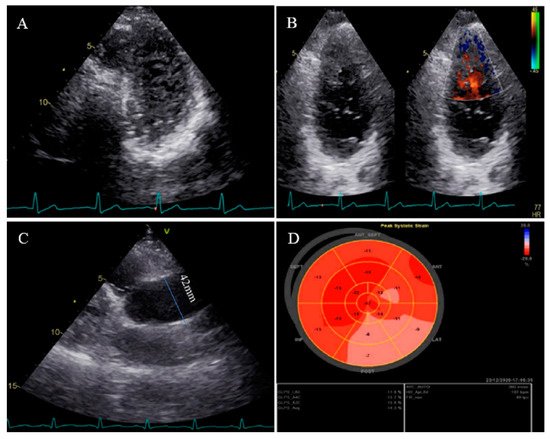

2.2. Case #2. NCLV, Patent Foramen Ovale (PFO), and Fast-Growing Aortic Aneurysm

A 56-year-old retired military general was referred with dyspnea on exertion for 3 months, which became worse over time. He had no underlying disease or cardiovascular risk factor. On physical examination, he had tachycardia and tachypnea and used accessory muscles of respiration, and on cardiac auscultation, an audible left-sided S3 gallop with “tic-tac” heart sounds was detected. On ECG, he had sinus tachycardia, low voltage QRS complex, and poor R progression in the precordial leads. TTE showed NCLV with severe global hypokinesia (LVEF = 16%), dilated aortic root and proximal ascending aorta (diameter = 49 mm; indexed = 23 mm), and effacement, in addition to the presence of PFO. A genetic study showed mutations in the DSP (e.3857_3859del: p.1286_1287del.), TTN (c.C80492T: p. P26831L), and DSC2 (c.A1886G:p.N629S) genes. A 6-month follow-up TTE showed a fast-growing aortic root aneurysm that reached 58 mm (indexed = 28 mm), although the patient was receiving beta-blockers and had no clinical symptoms. STE showed impaired myocardial performance with relative apical sparing and coronary angiography with the left ventricle and aortic root cineangiography showed dilated LV with remarkable recesses and dilated aortic root (6.25 cm) (Figure 2). The patient was scheduled for a valve-sparing aortic root replacement surgery (David procedure). The perioperative and postoperative TEE showed normal functioning native aortic valve with minimal aortic insufficiency and no aortic stenosis. At the follow-up visit, the patient had no clinical symptoms related to heart failure. The family members refused genetic study because of the high costs of the test (not covered by the insurance).

Figure 2.

Two- and three-dimensional transthoracic echocardiographic views of case #2: (A–C); left ventricular apical four and two-chamber views. (D,E); Apical SAX view, illustrating hypertrabeculated apical portions in addition to deep intertrabecular recesses and reduced left ventricular ejection fraction (LVEF = 16%, calculated by Simpson’s method). (F); Color Doppler echocardiography, showing evidence of direct blood flow from the ventricular cavity into deep intertrabecular recesses. (G,H); Transesophageal echocardiographic findings of baseline (left) and 6 months later (right); follow-up test showed fast-growing aortic root that reached 5.8 cm. (I); Speckle tracking echocardiographic findings, compatible with myocardial performance impairment plus relative apical sparing (GLS = −10.4%).